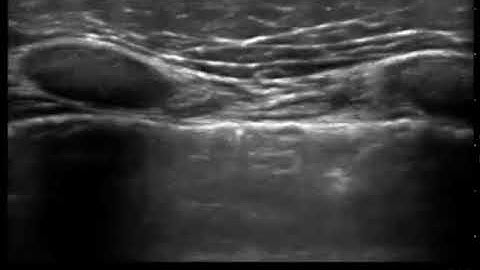

M Mode for Lung Ultrasound - Lung Sliding